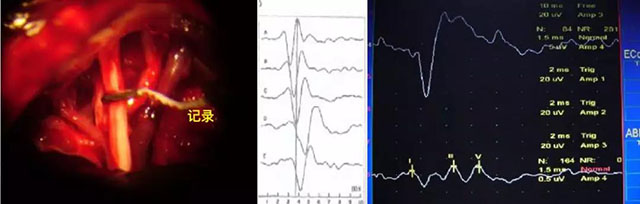

↓术中电生理监测举例↓

听神经动作电位

术中神经电生理监测是指应用各种神经电生理技术来监测手术中处于危险状态的神经系统功能完整性的一门技术。

※尽早发现和辨明由于手术造成的神经损害,并迅速纠正损害的原因,避免永久性的神经损伤,提高医疗质量。

※协助手术医师鉴别不明确的组织,特别是那些穿过或围绕在组织或肿瘤上的神经纤维。

※协助手术医师鉴别神经受损害的部位、节段,并检查受损的神经或者神经束是否还有功能。

※提供给手术医师神经电生理监测的依据,使手术者明白正在进行的手术步骤会不会造成神经的损伤。